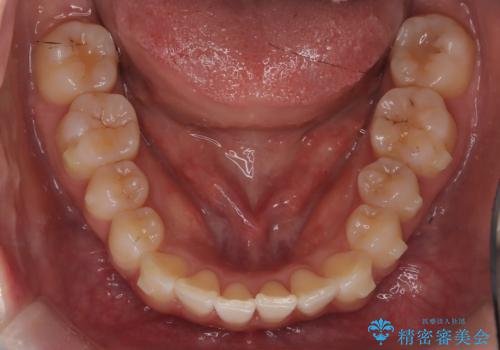

前歯のガタつきをマウスピース矯正で改善

- 前歯のガタツキが気になると来院されました。

奥歯の噛み合わせは綺麗に噛んでいたため、前歯の叢生(でこぼこ)に集中して治療するように計画しました。